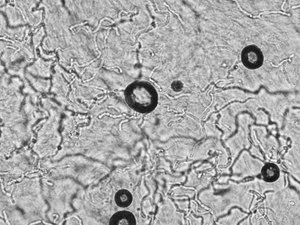

この方の水虫菌は、このように見えました(下写真:菌糸↑、胞子↑↑)![]()

なぜここまで爪水虫菌(白癬菌)の確認にこだわるかというと、爪水虫そっくりな病気がたくさんあるからなんです。見た目だけでは鑑別できません。塗り薬くらいならまだしも、菌の確認もせず水虫の内服薬を開始してはいけません

ちなみに白癬菌は、顕微鏡で下写真のように見えます。当院では、実際にモニターで見せて患者さんに納得してもらってから治療を開始します。

糸状菌(filamentous fungi)の一種で、菌糸が糸(filament)のように見えます。ちなみに丸いのは空気の泡です。